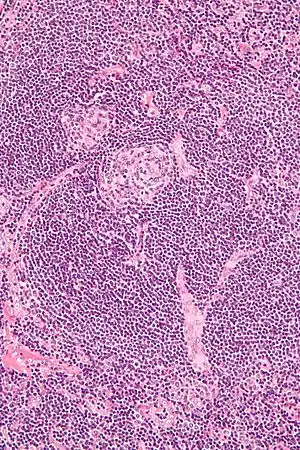

| Micrograph of Castleman disease showing hyaline vascular features including atrophic germinal center, expanded mantle zone, and a radially penetrating sclerotic blood vessel ("lollipop" sign). H&E stain. | |

Castleman disease is defined by a range of characteristic features seen on microscopic analysis (histology) of tissue from enlarged lymph nodes.[10] Histologic features consistent with Castleman disease are categorized into common patterns:

- Hyaline vascular: regressed germinal centers, follicular dendritic cell prominence or displasia, hypervascularity in interfollicular regions, sclerotic vessels, prominent mantle zones with an “onion-skin” appearance.[11]

UCD most commonly demonstrates hyaline vascular features, but plasmacytic features or a mix of features may also be seen.[7] iMCD more commonly demonstrates plasmacytic features, but hypervascular features or a mix of features are also seen. All cases of HHV-8-associated MCD are thought to demonstrate plasmablastic features—similar to plasmacytic features, but with plasmablasts present.[10] The clinical utility of subtyping Castleman disease by histologic features is uncertain, as histologic subtypes do not consistently predict disease severity or treatment response.[10]